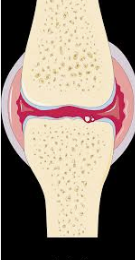

주로 통증이 발생하는 부위는 관절이 많으며 일반적으로는

만성 류머티즘성 관절염이라고 한 번쯤 들어보셨을 거예요.

다양한 편인데 자고 일어나면 관절이나 근육이 많이 굳어있고

특히 목이나 어깨 무릎 같은 부위에 통증이 심한 경우가 많습니다.